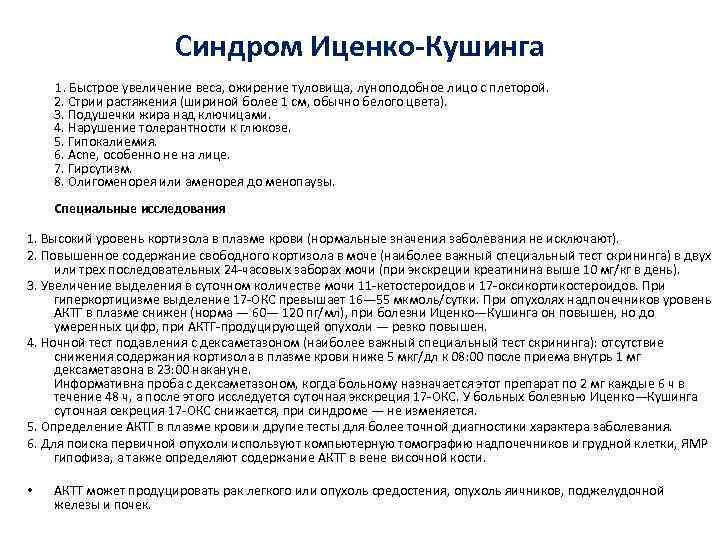

Синдром Иценко-Кушинга 1. Быстрое увеличение веса, ожирение туловища, луноподобное лицо с плеторой. 2. Стрии растяжения (шириной более 1 см, обычно белого цвета). 3. Подушечки жира над ключицами. 4. Нарушение толерантности к глюкозе. 5. Гипокалиемия. 6. Acne, особенно не на лице. 7. Гирсутизм. 8. Олигоменорея или аменорея до менопаузы. Специальные исследования 1. Высокий уровень кортизола в плазме крови (нормальные значения заболевания не исключают). 2. Повышенное содержание свободного кортизола в моче (наиболее важный специальный тест скрининга) в двух или трех последовательных 24 -часовых заборах мочи (при экскреции креатинина выше 10 мг/кг в день). 3. Увеличение выделения в суточном количестве мочи 11 -кетостероидов и 17 -оксикортикостероидов. При гиперкортицизме выделение 17 -ОКС превышает 16— 55 мкмоль/сутки. При опухолях надпочечников уровень АКТГ в плазме снижен (норма — 60— 120 пг/мл), при болезни Иценко—Кушинга он повышен, но до умеренных цифр, при АКТГ-продуцирующей опухоли — резко повышен. 4. Ночной тест подавления с дексаметазоном (наиболее важный специальный тест скрининга): отсутствие снижения содержания кортизола в плазме крови ниже 5 мкг/дл к 08: 00 после приема внутрь 1 мг дексаметазона в 23: 00 накануне. Информативна проба с дексаметазоном, когда больному назначается этот препарат по 2 мг каждые 6 ч в течение 48 ч, а после этого исследуется суточная экскреция 17 -ОКС. У больных болезнью Иценко—Кушинга суточная секреция 17 -ОКС снижается, при синдроме — не изменяется. 5. Определение АКТГ в плазме крови и другие тесты для более точной диагностики характера заболевания. 6. Для поиска первичной опухоли используют компьютерную томографию надпочечников и грудной клетки, ЯМР гипофиза, а также определяют содержание АКТГ в вене височной кости. • АКТТ может продуцировать рак легкого или опухоль средостения, опухоль яичников, поджелудочной железы и почек.

Синдром Иценко-Кушинга 1. Быстрое увеличение веса, ожирение туловища, луноподобное лицо с плеторой. 2. Стрии растяжения (шириной более 1 см, обычно белого цвета). 3. Подушечки жира над ключицами. 4. Нарушение толерантности к глюкозе. 5. Гипокалиемия. 6. Acne, особенно не на лице. 7. Гирсутизм. 8. Олигоменорея или аменорея до менопаузы. Специальные исследования 1. Высокий уровень кортизола в плазме крови (нормальные значения заболевания не исключают). 2. Повышенное содержание свободного кортизола в моче (наиболее важный специальный тест скрининга) в двух или трех последовательных 24 -часовых заборах мочи (при экскреции креатинина выше 10 мг/кг в день). 3. Увеличение выделения в суточном количестве мочи 11 -кетостероидов и 17 -оксикортикостероидов. При гиперкортицизме выделение 17 -ОКС превышает 16— 55 мкмоль/сутки. При опухолях надпочечников уровень АКТГ в плазме снижен (норма — 60— 120 пг/мл), при болезни Иценко—Кушинга он повышен, но до умеренных цифр, при АКТГ-продуцирующей опухоли — резко повышен. 4. Ночной тест подавления с дексаметазоном (наиболее важный специальный тест скрининга): отсутствие снижения содержания кортизола в плазме крови ниже 5 мкг/дл к 08: 00 после приема внутрь 1 мг дексаметазона в 23: 00 накануне. Информативна проба с дексаметазоном, когда больному назначается этот препарат по 2 мг каждые 6 ч в течение 48 ч, а после этого исследуется суточная экскреция 17 -ОКС. У больных болезнью Иценко—Кушинга суточная секреция 17 -ОКС снижается, при синдроме — не изменяется. 5. Определение АКТГ в плазме крови и другие тесты для более точной диагностики характера заболевания. 6. Для поиска первичной опухоли используют компьютерную томографию надпочечников и грудной клетки, ЯМР гипофиза, а также определяют содержание АКТГ в вене височной кости. • АКТТ может продуцировать рак легкого или опухоль средостения, опухоль яичников, поджелудочной железы и почек.